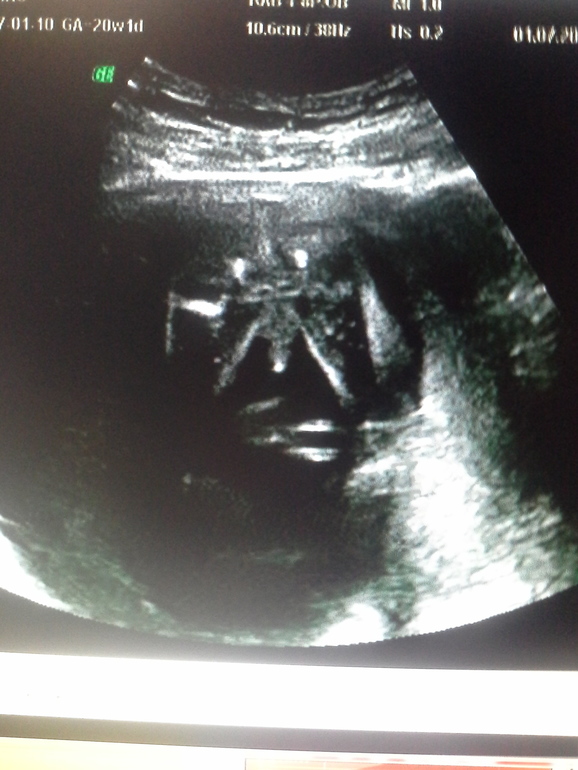

Наше второе узи, помогите по фото определить пол))

УЗИ, КТГ, доплерДевочки,была на втором плановом узи!С нашей бусинкой все в порядке,все соответствует сроку: положение плода продольное, бпр 46мм, ог 169мм,ож 137 мм, дб 29мм, плацента по передней стенке 23 мм, нормальная. Количество вод нормальное, длина ш/матки 40мм, вес плода 270 г. Единственное не указали ктр...Беременность 19нед.3 дня. И нам предположили(правда совсем неуверенно) девочку! Дорогие мои,посмотрите пожалуйста,хотелось бы все-таки знать наверняка)Очень уж хочется начать делать приятные покупочки)))